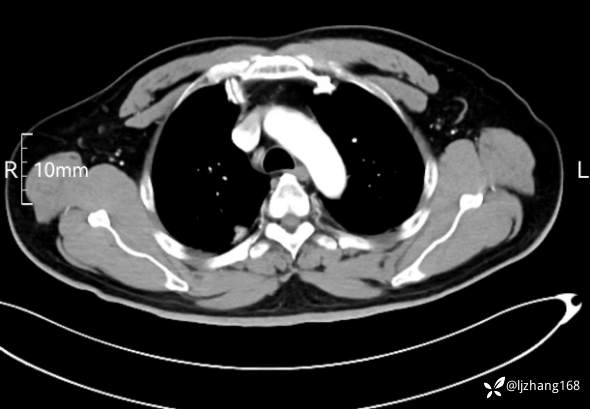

中年男患,右肺团片影,炎症0R肿瘤?

简要病史: 20+天前患者因受凉后出现阵发性咳嗽,咳少量白色粘痰,痰易咳出,伴活动后气短,伴纳差、乏力、全身酸痛,伴多汗,无痰中带血及咯血,无发热、畏寒及寒战,无潮热、盗汗,无夜间阵发性呼吸困难及端坐呼吸,无声嘶,无头晕、头痛,无黑矇、晕厥及意识障碍,无腹痛、呕血及黑便等不适,遂就诊于当地医院予以输液等治疗后未见明显好转(具体诊疗不详),现为进一步诊治就诊于我院门诊,以“右肺占位”收入我科。病来饮食欠佳,近期体重下降(具体不详)。既往糖尿病病史7+年,未规律监测血糖,血糖控制不佳。否认“高血压、冠心病及慢性肾脏病”等慢性疾病史。否认“肝炎、结核、伤寒”等传染病史。否认食物、药物过敏史。否认外伤、输血史,预防接种史不详。

辅助检查:糖化血红蛋白12.3%。肺炎支原体IgG、IgM、呼吸道合胞病毒均未见明显异常。胸部CT:右肺上叶阻塞性肺炎。